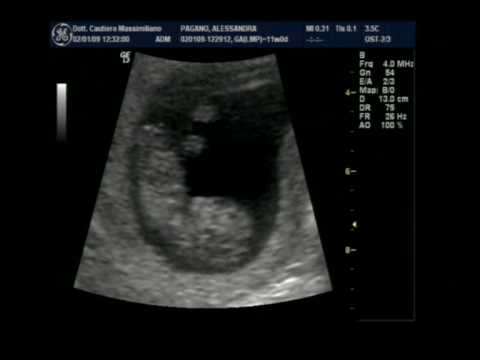

11esima settimana. Si sente il battito. Ci sono le mani e i piedi. Gli organi si sviluppano. C'è tutto. Non serve aggiungere altro.